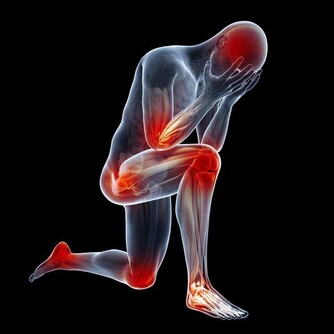

糖尿病患者由於存在代謝紊亂,加上血糖高、排尿多,以及糖尿病對微血管及末梢神經的損害,他們的皮膚黏膜常處於慢性脫水、缺氧和營養不良的狀態,比普通人體表更乾燥、彈性減退、表皮纖薄,再生能力與抗感染的屏障作用均降低,故易患多種皮膚病並不奇怪。如果皮膚瘙癢反復不愈應及時讓內分泌科醫生排除糖尿病可能。

糖尿病足:高血糖導致下肢血管、神經系統病變,一旦皮膚稍有破損、感染而不及時感知或治療,將會迅速形成潰瘍、壞疽,最終不得不做截肢處理,造成病人身體上、心理上雙重打擊,生活質量大大下降,嚴重的甚至還會危及生命。